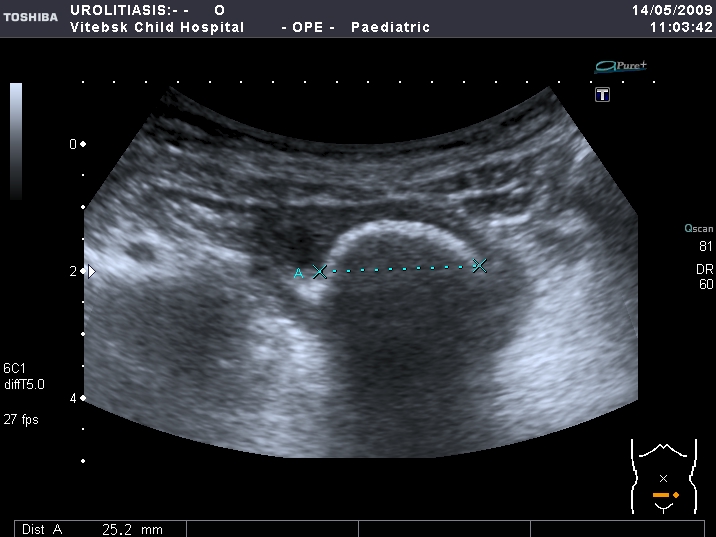

Правая почка

Левая почка

Нейрогенный мочевой пузырь (?), МКБ, конкремент мочевого пузыря, двухсторонний мегауретер, конкремент правой почки.

Через 6 месяцев при контрольном УЗИ - сохраняются камни в правой почке прежних размеров. Собирательная система левой почки не расширена.